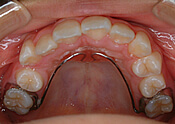

乳歯~混合歯列の矯正装置

使用装置は永久歯の矯正装置とは異なります。

症例によって様々ですが、基本的に歯の裏側につける目立たないもの、または取り外しのできるもの(可撤式)が多いです。

お子様の性格に合わせて固定式、可撤式など選択肢は多数ご用意しています。